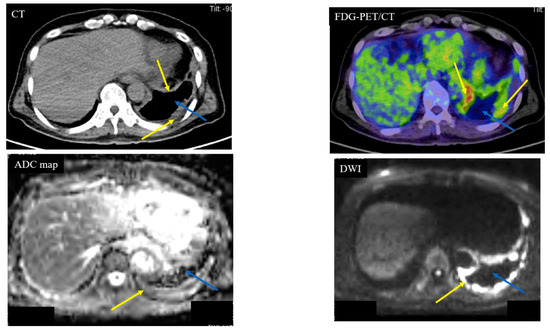

| Pleural dissemination | 1 | 9 | 0 | 0 | 10 | |